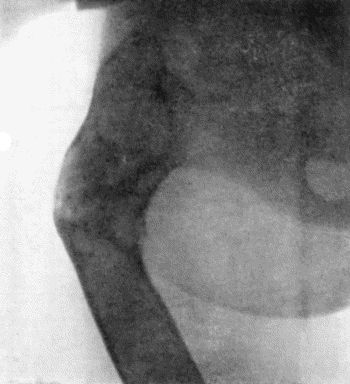

137.Radiogram of Upper End of Femur in Osteomyelitis Fibrosa 478